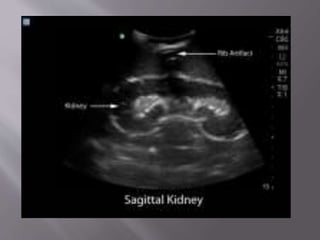

 Indications:  Biopsy of afocal solid lesion /suspicious cystic lesion for diagnosis.  Nonfocal biopsy to evaluate for nephropathy or renal transplant rejection

• 64.

 US has theadvantages of real-time needle placement  No radiation & is therefore well suited for most nonfocal renal biopsies in thin pts and in biopsies of some focal solid masses or cystic masses .

• 65.

 The patient isplaced in the prone position and the biopsy is typically taken from the lower pole of the kidney if there are no specific locations of interest.

• 66.

 The biopsy needleis guided using ultrasound to ensure visualization of the needle as it pierces the kidney parenchyma.

• 67.

 Care is takennot to enter the collecting system (as it would result in haematuria) or to go near the renal hilum (to prevent injury to the vessels).